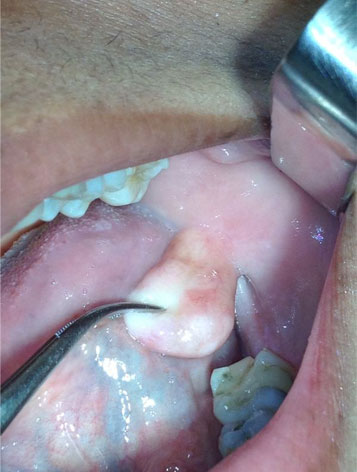

Sin embargo, los tumores malignos de la cavidad oral requieren para su diagnóstico una biopsia y un estudio patológico. Antes de la cirugía, se deben estudiar con resonancias, tac y demás estudios para determinar con exactitud la extensión de estructuras anatómicas afectadas por el carcinoma.

La cirugía oncológica de la cavidad oral se basa en la extirpación del tumor con límites de seguridad, la extirpación de los posibles ganglios linfáticos afectados -incluidas sus cadenas-, y la reconstrucción de la estética y función, tanto de la cara como labio, mandíbula o lengua, para lo que utilizamos colgajos miofasciales o micro quirúrgicos.